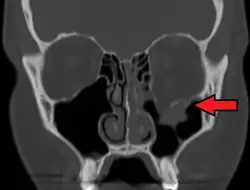

Fracture du plancher de l'orbite gauche.

Une fracture du plancher de l'orbite est une fracture de l'os sur lequel est posé l'œil. C'est une fracture faciale fréquente. Le mécanisme est un choc direct sur l'orbite qui aboutit à une fracture du plancher.

Le diagnostic est fait sur le scanner facial.